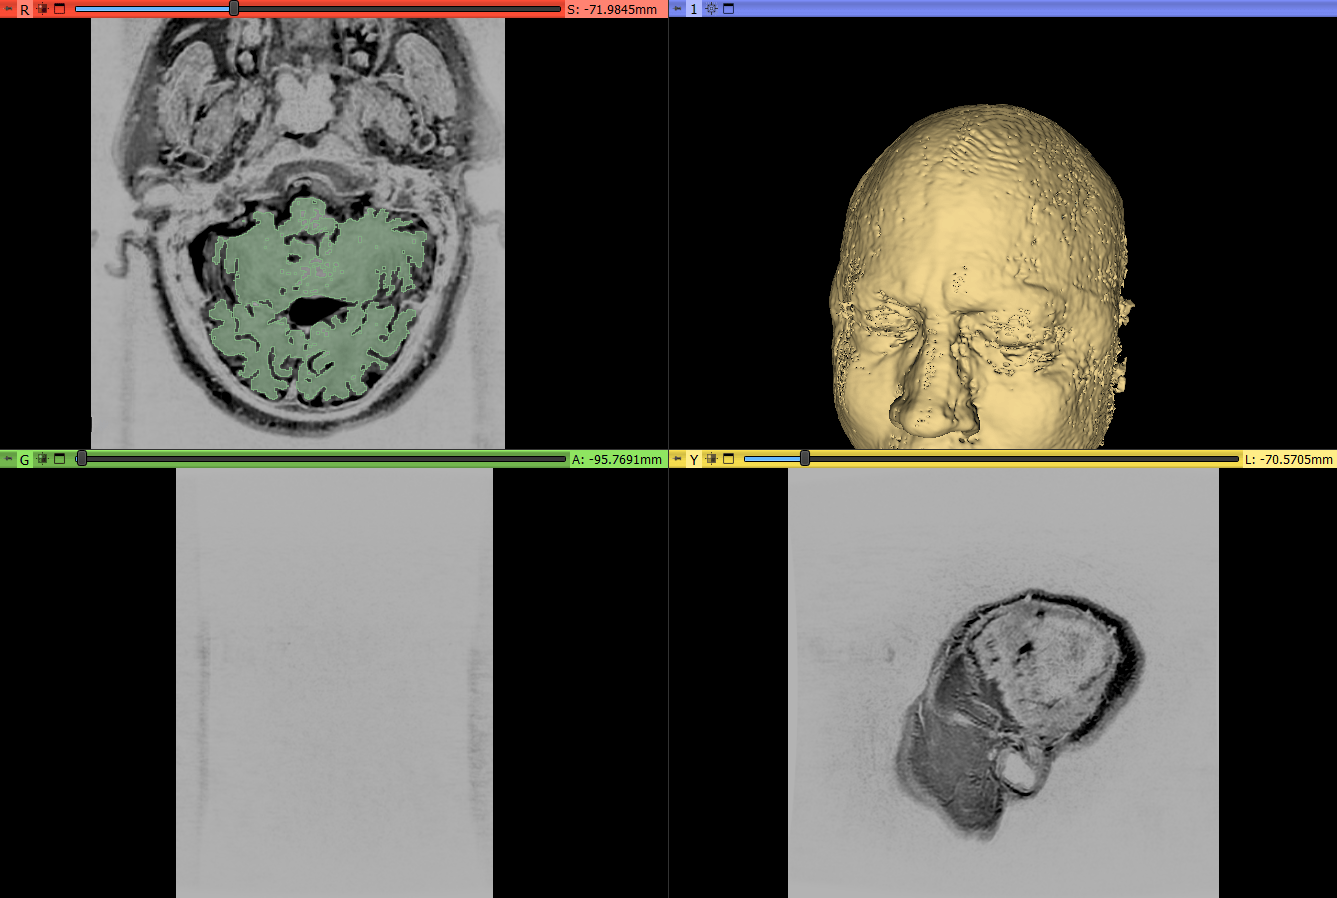

Most 3D modeling projects start with gathering reference images, building an inspiration board, and collecting all important files before modeling in ZBrush. In this case, I received an MRI scan in .dicom format, which ZBrush can’t read. So the first step was finding compatible software. After some deep diving on Google, testing multiple softwares, and watching tutorial videos, I was able to properly convert and import the scan into ZBrush.

BONUS: Here’s what a meninges (muh·nin·jeez) look like, the membrane that surrounds the brain